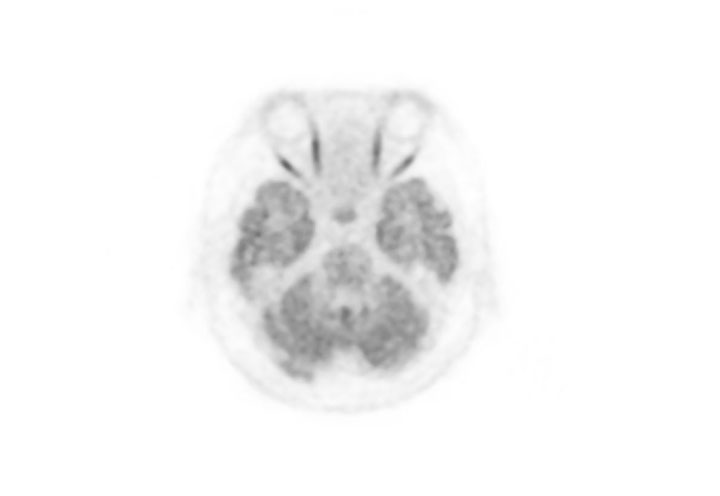

Head / Case3 : FDG

Axial

Courtesy : Kindai University Hospital

- Imaging protocol

- Injected dose: 4.49 MBq/kg, 18F-FDG

- Uptake time: 46 minutes

- Scan time: 30 minutes